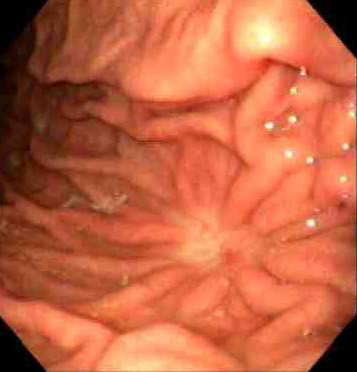

Seen above are gastric ulcers of small, medium, and large size on upper endoscopy. All gastric ulcers are biopsied, since gross inspection alone cannot determine whether a malignancy is present. Smaller, more sharply demarcated ulcers are more likely to be benign. |